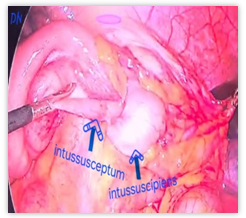

The patient was immediately scheduled for laparoscopic intussusception reduction. Intraoperatively, an ileo-colic intussusception was noted [fig. 3A]. The intussusception was reduced laparoscopically.

Fig. 3A-D: Photograph showing ileo-colic intussusceptions